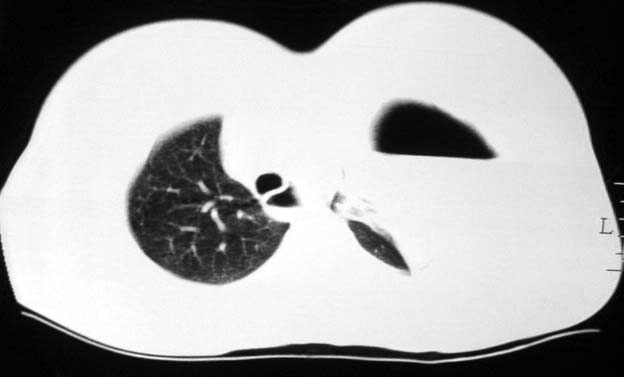

标题: CT5517:女性、24岁,反复胸痛、气促不能平卧半月。 [打印本页]

标题: CT5517:女性、24岁,反复胸痛、气促不能平卧半月。

左肺可见二个含气或液气的囊状影,左肺段支气管、左肺动脉显示不清,纵隔右移,考虑:左肺支气管肺囊肿,左肺发育不良,纵隔疝。

左侧气液腔与胃腔影相连,考虑膈疝。钡餐检查有助于诊断。

我看这是膈疝,在纵隔窗第六\\七幅图像上可见胃粘膜影,再者可见两个腔影,这在液气胸是不会有的.

液气胸 怎么会有2 个大腔?

还是个膈疝